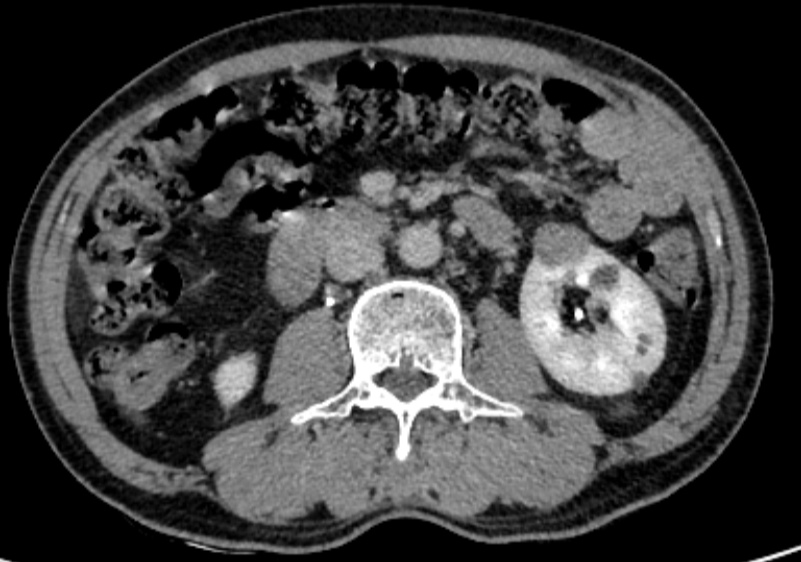

患者是一名60多岁男性,因“CT发现左肾占位”入院,完善泌尿系增强CT示“左肾肿瘤,考虑恶性可能”。

腹部增强CT